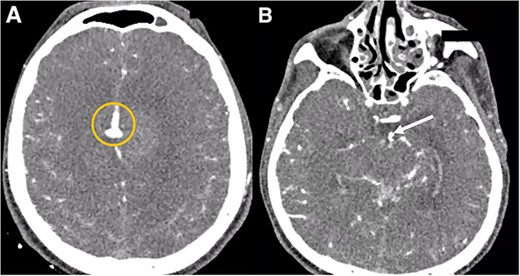

A multislice computed tomography (CT) without contrast revealed an extensive interhemispheric hematoma in the frontoparietal region, subarachnoid hemorrhage, and intraventricular hemorrhage in the adjacent area (Fisher grading score of IV) (Fig. 1). In addition, cerebral angiotomography and 3D reconstruction imaging suggested the presence of two abnormal vascular lesions: (i) a fusiform aneurysm of 12 × 7 mm in an accessory A2 portion of the ACA and (ii) an unruptured saccular aneurysm of 3.3 × 2.8 mm in the distal segment of the basilar artery adjacent to the anterolateral surface of the P1 segment and the left superior cerebellar artery (Figs 2 and 3).

Cerebral angiotomography. (A) Axial cut depicts a midline irregular vascular lesion (yellow circle). (B) Axial cut shows a small saccular aneurysm at the basilar artery (white arrow).